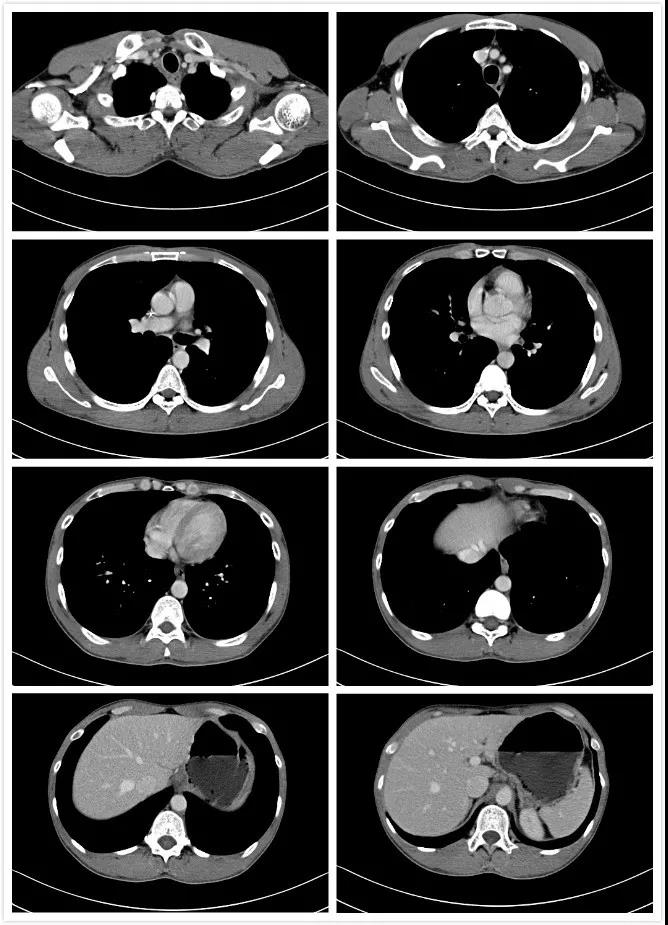

2020年5月11日

颈胸腹部CT示:1、食管下段(肺静脉下方水平)管壁稍增厚,结合病史,符合食管癌,病变范围较旧片明显缩小,请结合临床。双侧胸廓入口、肝胃间隙及上腹膜后多发小及轻度肿大淋巴结,较旧片明显缩小。2、双侧颈部数个小淋巴结征。3、双肺少许慢性炎症,右肺尖病变略呈磨玻璃改变,较旧片增多,建议定期复查除外其他。4、肝左叶小钙化或小结石;肝内多发血管瘤可能,建议随诊复查;门静脉轻度增宽。5、胆、胰、脾未见明显占位性病变。6、所摄入左侧肾上腺增生可能,较旧片大致相仿,建议随诊复查。